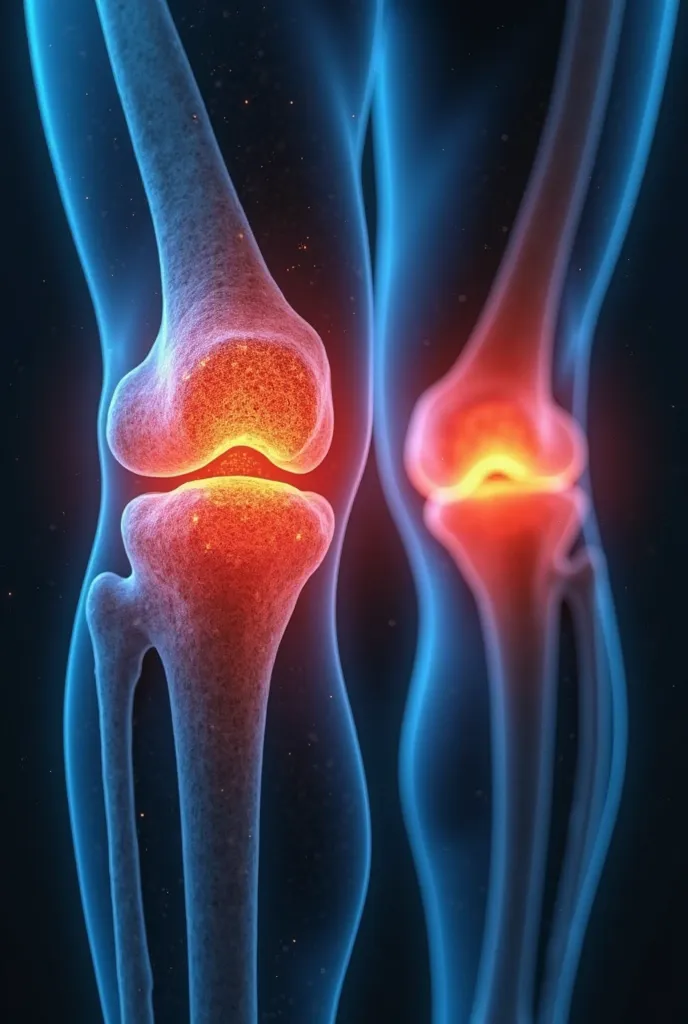

A close up of a white object with a human leg

Close-up of human knee,There is a bone in the middle, knee, Knees, surreal bone structure, Protruding bones, Realphotos, orthographic view, Look across the shoulder, medical depiction, Osteoarticular joints, computer generated, hyper realisitc, sharp bone structure, joint, digital painted

Close-up of human knee

knee

,

Knees

medical depiction

Osteoarticular joints